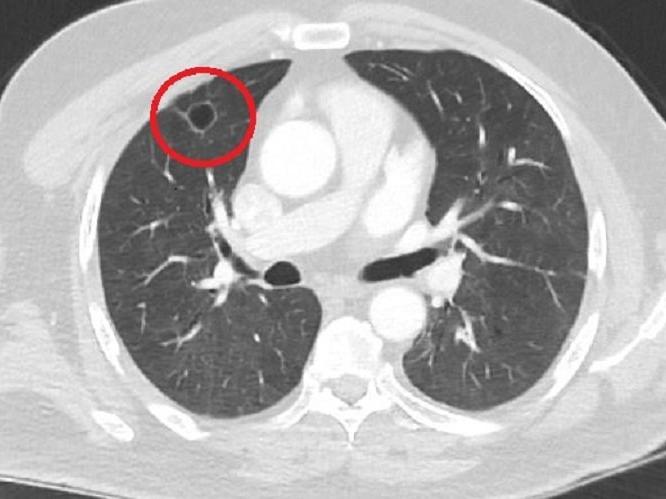

- Hastamız, çalıştığı başka bir kentte göğsünden darbe alıyor ve ağrıları geçmeyince bir üniversite hastanesine başvuruyor. Burada hastaya bir akciğer grafisi çekiliyor. Sağ akciğerinde bir kitleye rastlanıyor. Daha sonra hastaya, bir akciğer tomografisi çekiliyor ve göğüs cerrahisi için önemli büyüklükte olan 4 santimetre çapında, akciğer kanserine benzer özellikte radyolojik bulgular olan bir kitle tespit ediliyor. Daha sonra hastaya yapılan ileri tetkiklerde akciğer kanseri teşhisi konuluyor. Hastaya bir cerrahi planlanıyor.

- 14'üncü gün tekrar bize başvurdu ve yapılan PCR testi negatif çıktı. Yeni bir tomografi çektik ve tümörün tamamen ortadan kalktığını gördük. Şimdi sonuç bilgilerinden başlangıca gittiğimizde, bu bir akciğer kanseri olsaydı, ortadan kalkması mümkün değildi. Başka bir patolojiye bağlı durum olsaydı, yine verdiğimiz tedaviyle ortadan kalkmasını çok beklemeyiz. Antiviral tedavisi verdik ve hastanın radyolojik bulguları neredeyse tamamen normale döndü. Hastaya bunu izah ettik, 'Dünya literatüründe hiç görülmeyen bir radyolojik bulgu' diyerek. Bu gördüğümüz manzara artık hastanın akciğer grafisinde yok, akciğer kanseri değil.

Genel olarak dünya literatürüne baktığımızda virüsün akciğer bulguları, radyolojik bulguları infiltrasyon, buzlu cam dansitesi gibi bilinen bulgular. Ama bizim hastamızda akciğer tümörünü taklit eden bir kitle vardı. Ve biz bunu dünya literatüründe hiç görmemiştik. Bununla ilgili geniş çaplı bir araştırma yaptım. Hem kendi deneyimlerimden hem kendi hastanemizde yatan hastalardan yola çıkarak birçok hastanın radyolojik bulgularına baktık. Dünya literatürlerini karıştırdım, diğer arkadaşlarıma danıştım, benzeri bulguya rastlamadım. (DHA)